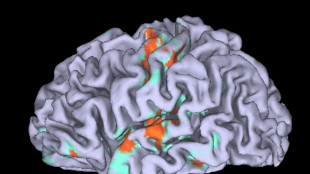

Uno studio spiega come il cervello 'costruisce' la percezione del tempo

Processo è il risultato di più stadi di elaborazione. Ricerca della Sissa su Plos Biology

Cervello, l'immaginazione è più complessa del semplice 'replay' dei sensi

Attiva funzioni cognitive superiori per imparare, pianificare ed evitare pericoli

Svelato come la sclerosi multipla uccide i neuroni

L'infiammazione invade il cervello danneggiando il Dna della sostanza grigia